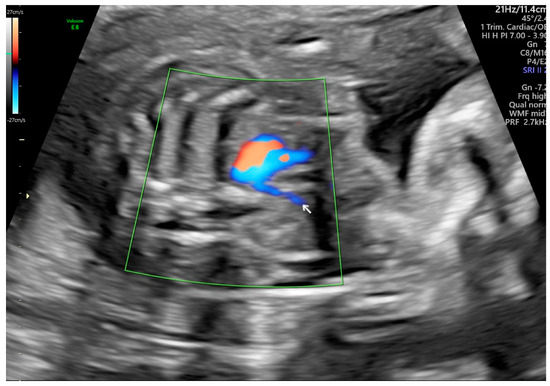

Comprehensive Analysis of the Aberrant Right Subclavian Artery: A Perspective from a Single Institute

4.1. Prenatal Diagnostic Techniques and Standardization